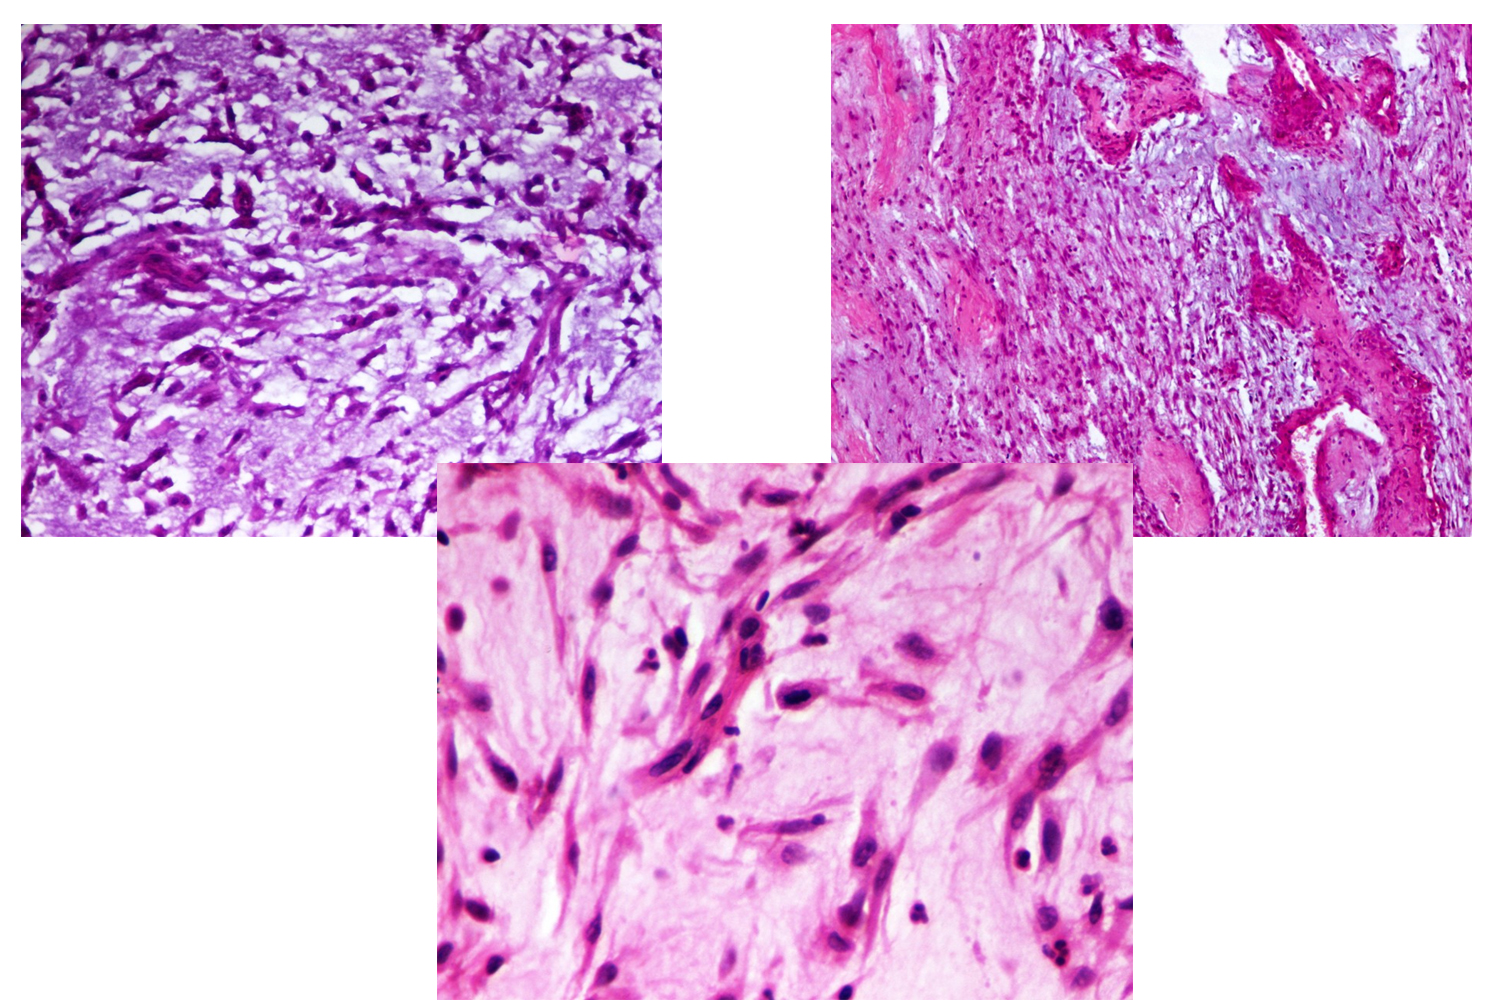

Myxoid Leiomyosarcoma. A, The Tumor Has An Infiltrative Growth Pattern

www.researchgate.net

www.researchgate.net

leiomyosarcoma myxoid tumor infiltrative growth leiomyoma necrosis tumors myometrium hypocellular abundant uterus eosin minimal atypia hematoxylin magnifications

leiomyosarcoma uterus myxoid pathology webpathology comments

Webpathology.com: A Collection Of Surgical Pathology Images

www.webpathology.com

www.webpathology.com

leiomyosarcoma uterus myxoid pathology webpathology stroma comments

Webpathology.com: A Collection Of Surgical Pathology Images

www.webpathology.com

www.webpathology.com

uterus leiomyosarcoma myxoid webpathology multinucleated